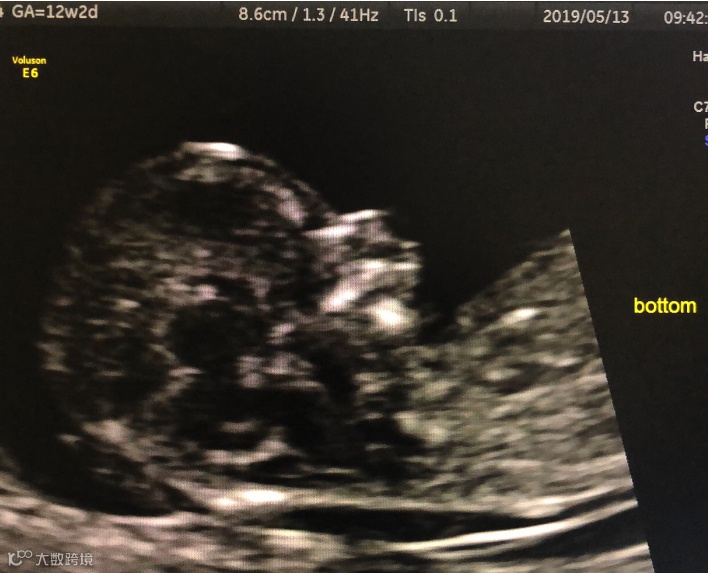

12+周 IVF双胎之一小下颌(对比下图)

12+周 同一病例另一胎下颌正常(对比上图)